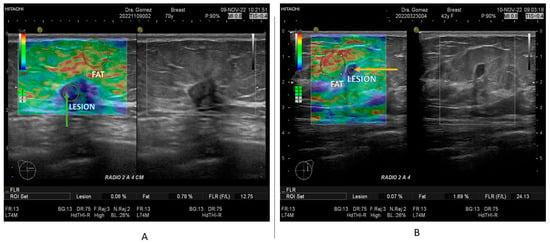

2.2. Ultrasound and Strain Elastography